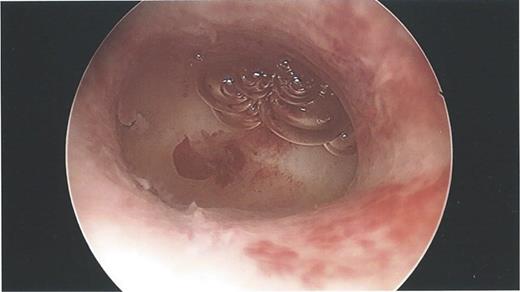

During the hysteroscopy 4 weeks later there was no evidence of an IUCD into the uterine cavity and no evidence of a perforation site in the uterus (Fig. 1). A laparoscopy followed, locating the coil threads deep in the Pouch of Douglas, with the IUCD perforating through the sigmoid colon into the lumen (Fig. 2). The IUCD was retrieved laparoscopically and the defect in the sigmoid colon was repaired by stapling the tear (Fig. 3).

Laparoscopy showing normal IUCD threads deep inside the Pouch of Douglas inside the sigmoid colon.